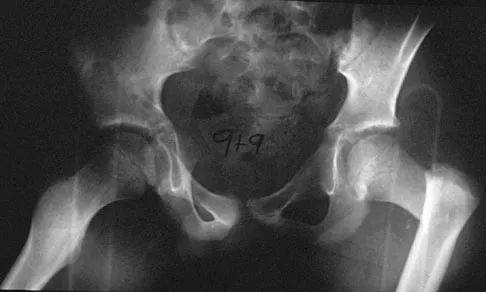

A 9-year-old child has right groin pain after falling from a tree. Examination reveals that the right leg is held in external rotation, and there is significant pain with attempts at passive range of motion. Radiographs are shown in Figures 43a and 43b. Management should consist of